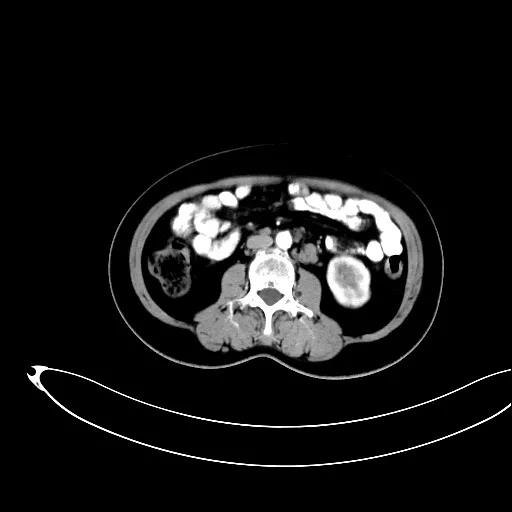

某患者因为“腹痛1周”而入院,外院B超提示子宫上方囊实性肿物,CT提示:左侧附件区占位,并盆腔及腹主动脉旁淋巴结转移。右肾动脉有右肾动脉及异位右肾动脉,其下均有肿大淋巴结。

排除禁忌后,在全麻下行“次广泛子宫切除+双附件切除+大网膜切除+阑尾切除术+盆腔淋巴结及腹主动脉旁淋巴结切除术”。术中切除腹主动脉左旁、右旁及后方淋巴结,达左右肾动静脉水平。多个淋巴结呈融合状态,长径约3-5cm。手术由陈亮副主任医师和宋趣清主治医师完成。

妇科一病区严格遵循指南推荐,在影像学或探查淋巴结阳性的晚期卵巢癌中,若能达到满意减瘤,仍常规行盆腔及腹主动脉旁肿大淋巴结切除/清扫术(如下图举例)。通过前期初步统计分析,肠系膜下动脉至肾静脉下淋巴结转移阳性率为25%左右,在全部腹主动脉旁淋巴结转移患者中约占30%,显示了肾静脉下腹主动脉旁淋巴结清扫的价值。其对生存的影响有待进一步观察。